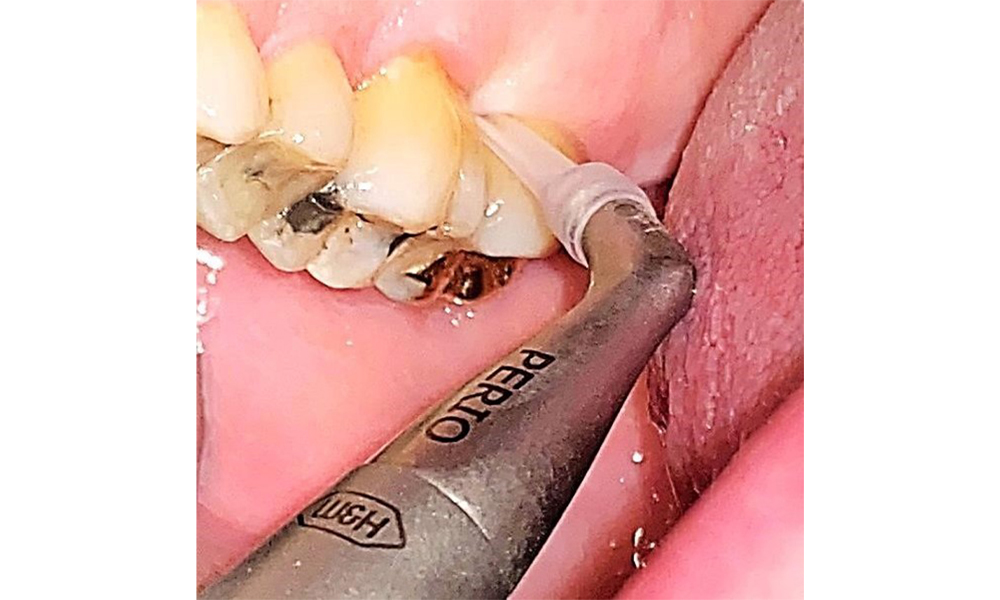

The documentation of periodontal findings, including pocket depth probing and bleeding status, is mandatory during each dental appointment due to the presence of periodontitis (Fig. 8). This will record the individual therapeutic needs and facilitate a rapid response to any progression of the pre-existing periodontitis.

Probing to document the findings in tooth 27 mesiopalatal. © Dr R. Krapf

Fig. 8: Probing to document the findings in tooth 27 mesiopalatal. © Dr R. Krapf

There are no limitations regarding the choice of instrumentation methods. Regular supragingival and subgingival instrumentation is essential to prevent disease progression due to the pre-existing periodontitis and high risk of recurrence. There are no limitations placed on the selection of instruments for mechanical biofilm removal from a general medical perspective, and removal should be performed as needed. Hard and mineralized plaque, such as calculus and concretions, should be removed using manual instruments or sonic/ultrasonic scalers (Fig. 9) (8, 9).

Use an ultrasonic tip to remove hard, mineralized plaque (Proxeo Ultra scaler with the Perio tip, W&H, shown here). © Dr R. Krapf

Fig. 9: Use an ultrasonic tip to remove hard, mineralized plaque (Proxeo Ultra scaler with the Perio tip, W&H, shown here). © Dr R. Krapf